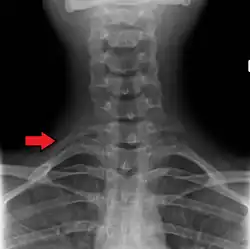

A C7 rib on the right

Variations in the number of ribs occur. About 1 in 200–500 people have an additional cervical rib, and there is a female predominance.[13] Intrathoracic supernumerary ribs are extremely rare.[14] The rib remnant of the 7th cervical vertebra on one or both sides is occasionally replaced by a free extra rib called a cervical rib, which can mechanically interfere with the nerves (brachial plexus) going to the arm.